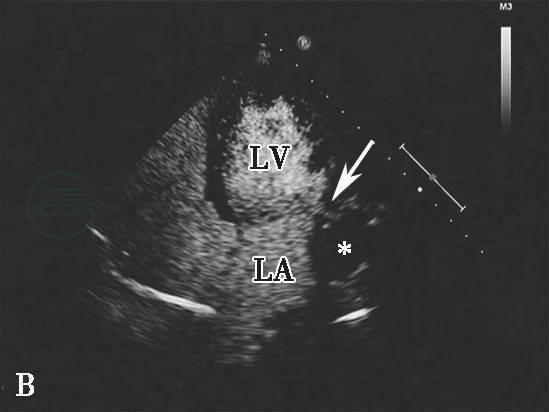

图2心肌梗死后左心室游离壁破裂合并假性室壁瘤形成二维切面图像

心尖四腔心切面显示左心室侧壁破裂形成巨大假性室壁瘤(星号示),其内可见附壁血栓(三角示)。LA.左心房;LV.左心室。